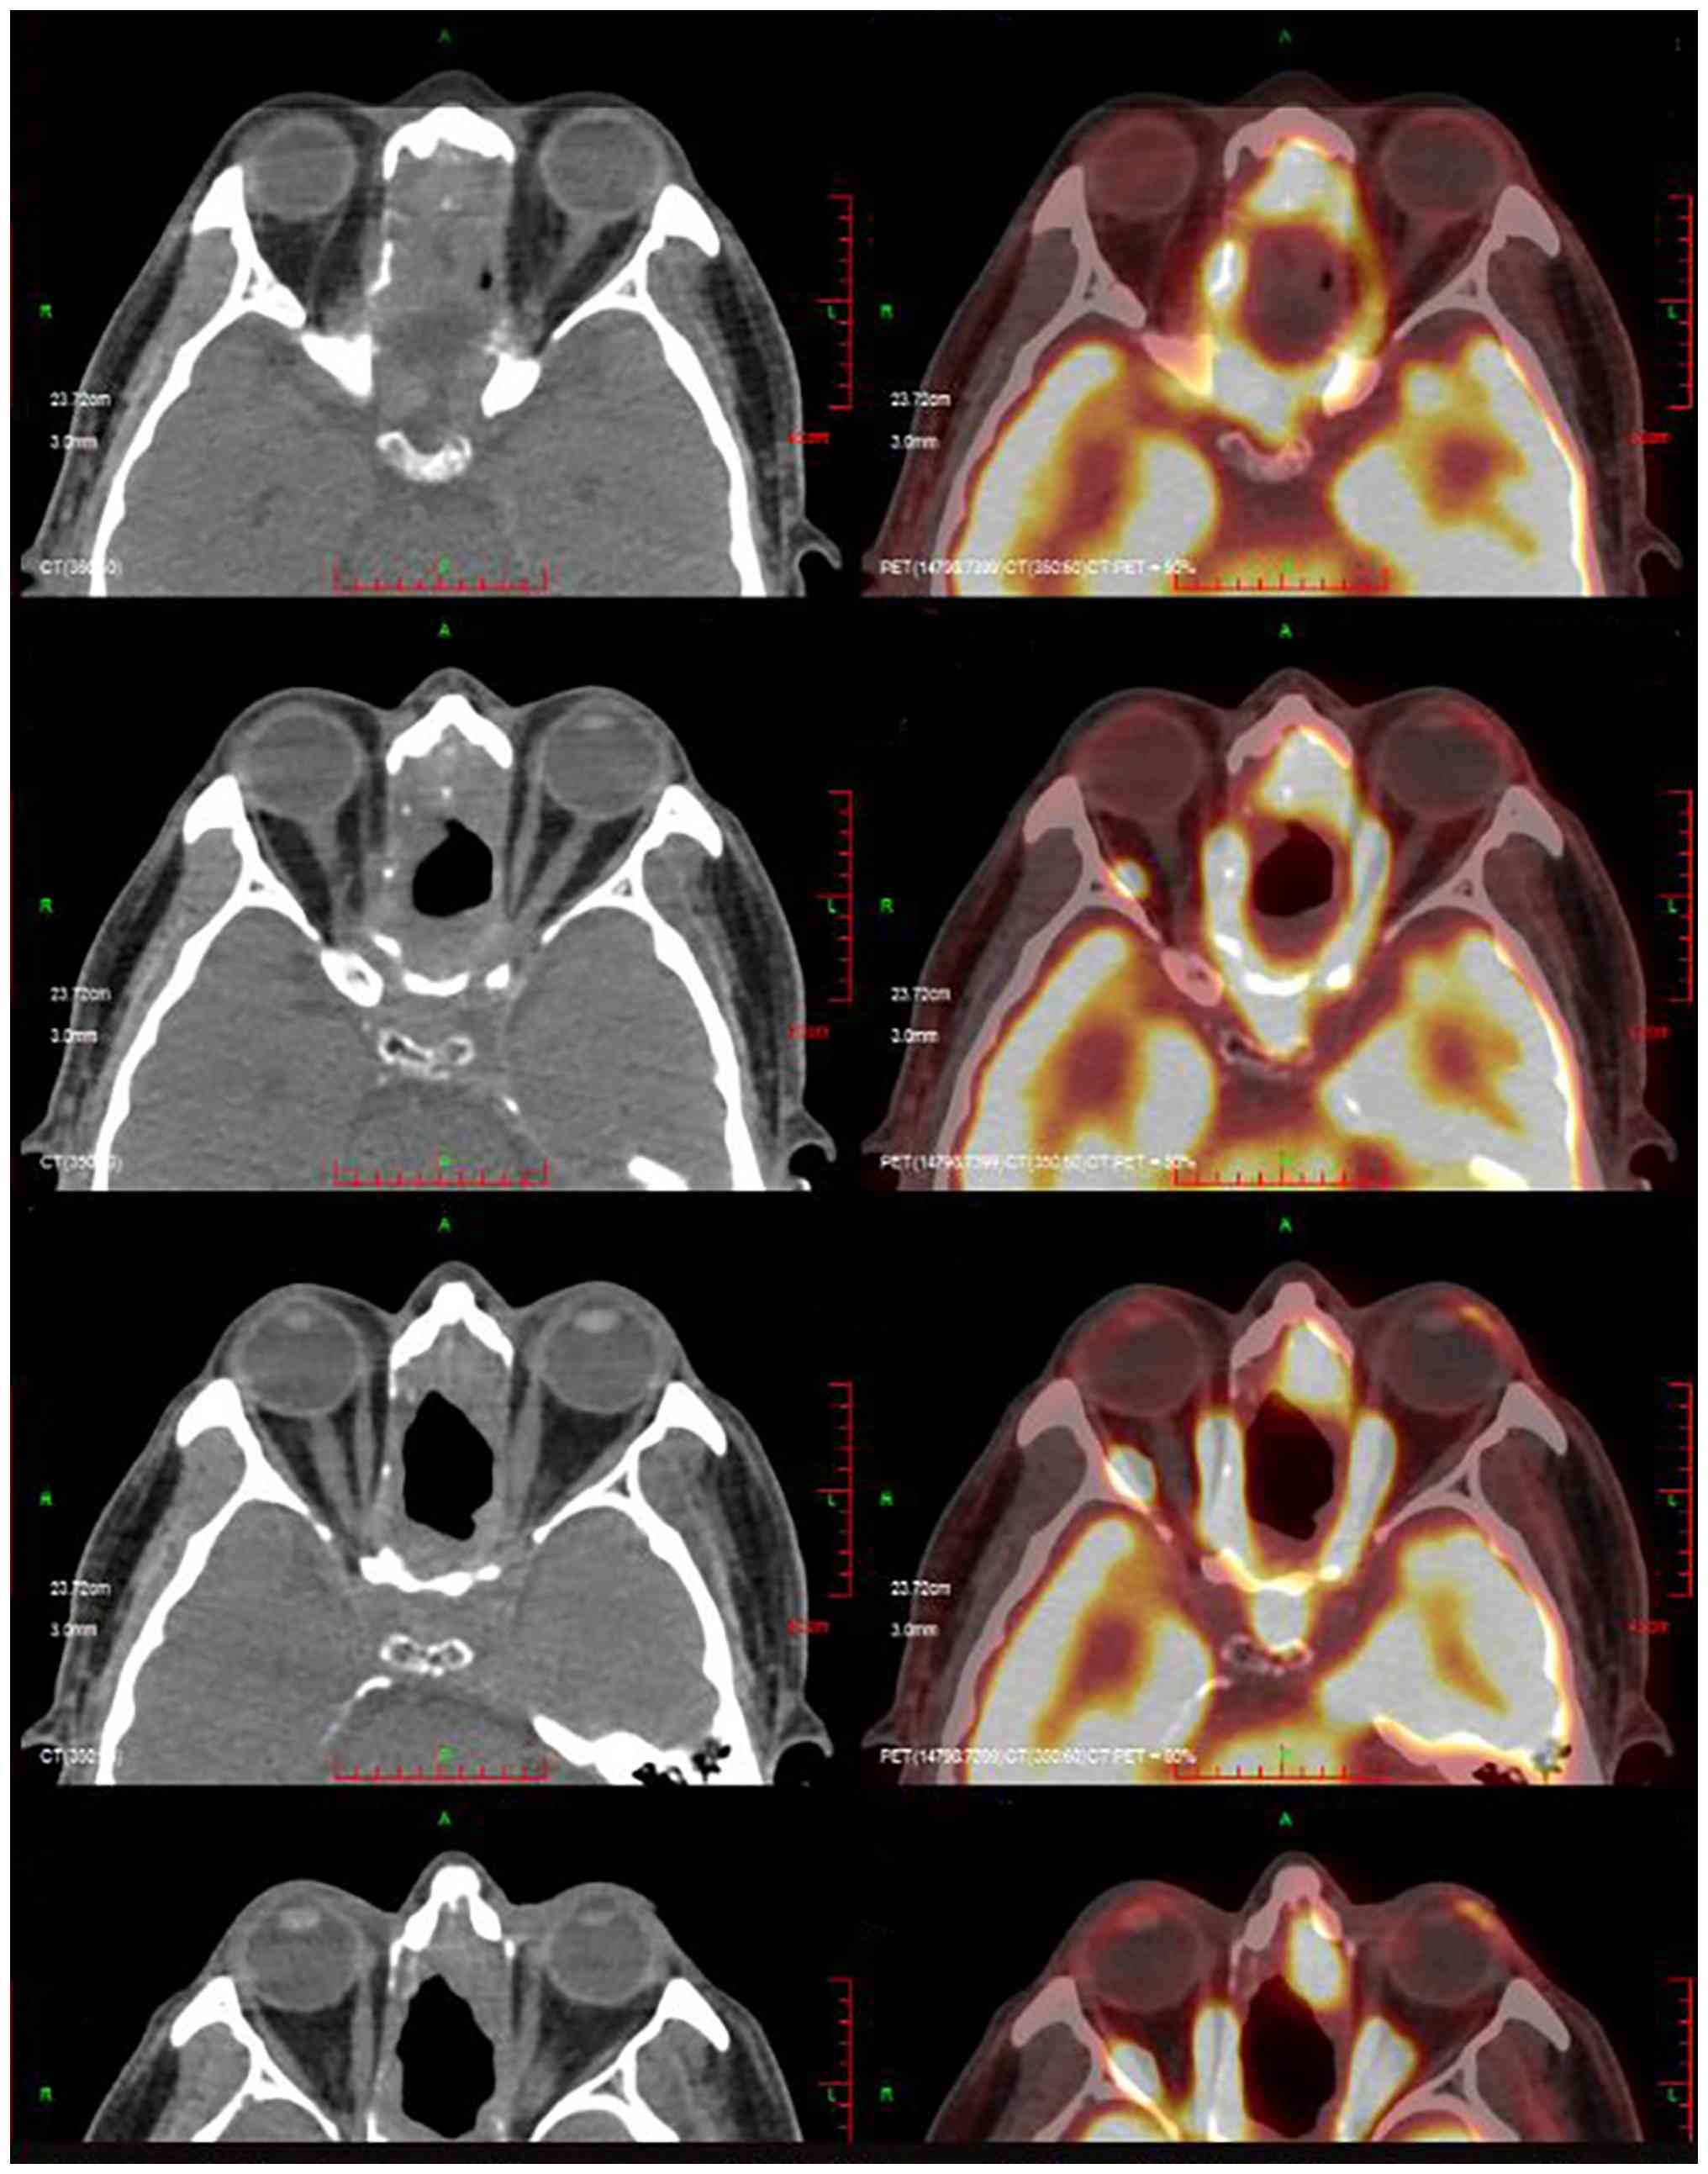

At 12 months post-surgery, the patient experienced bilateral vision loss, visual distortion, headaches, nausea and vomiting. A positron emission tomography-computed tomography (PET-CT) scan indicated tumor recurrence in the ethmoid and sphenoid sinuses, the anterior portion of the left nasal cavity and the nasal septum (Fig. 4). The biopsy results confirmed the presence of ITAC. Immunohistochemistry revealed PD-L1 expression with a combined positive score (CPS) of 5 and programmed cell death protein 1 (PD-1) positivity at 5% (22). The diagnosis of tumor recurrence, including PET-CT imaging and pathological biopsy, was confirmed at West China Hospital of Sichuan University. Systemic therapy was initiated with a regimen consisting of albumin-bound paclitaxel (300 mg on day 1), cisplatin (30 mg on days 1–3) and camrelizumab (200 mg on day 1) administered intravenously every 3 weeks for four cycles (3 weeks per cycle). Following four cycles of systemic therapy, grade II myelosuppression occurred (white blood cell count, 2.49×109/l; normal reference range, 3.5–9.5×109/l. The physical strength of the patient also markedly declined. The treatment regimen was adjusted to maintenance therapy with single-agent camrelizumab. The monotherapy schedule consisted of 200 mg camrelizumab administered once every 3 weeks. A total of 12 cycles were completed. The detailed course of treatment, including the initiation, adjustment and the duration of each therapeutic intervention, is summarized in a flowchart in Fig. 5. The Systemic therapy and the follow-up was based at the West China hospital and Dazhu People's Hospital.

Positron emission tomography-computed

tomography scan indicating tumor recurrence in the ethmoid and

sphenoid sinus, the anterior portion of the left nasal cavity and

the nasal septum (18F-fluorodeoxyglucose tracer).

Figure 4.

Positron emission tomography-computed tomography scan indicating tumor recurrence in the ethmoid and sphenoid sinus, the anterior portion of the left nasal cavity and the nasal septum (18F-fluorodeoxyglucose tracer).